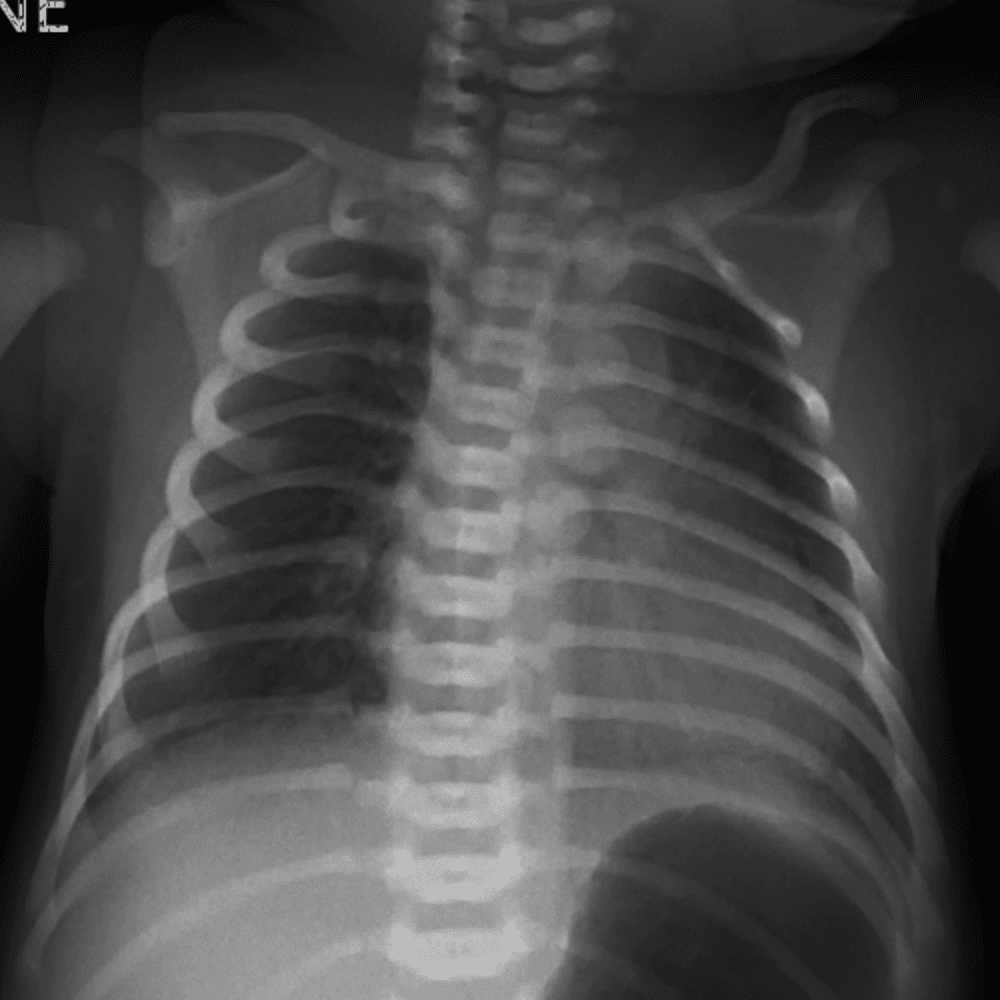

Peds Chest

Practice

Simulates call by including subtle or difficult cases and some normals.

50 cases